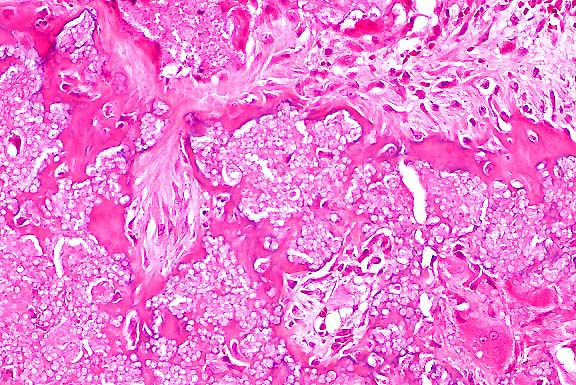

4x

obj

- Case 20-2. Bone. Irregular endochondral bone formation

occuring deep within cancellous bone. Dark cells in the lower

right are osteoclasts.